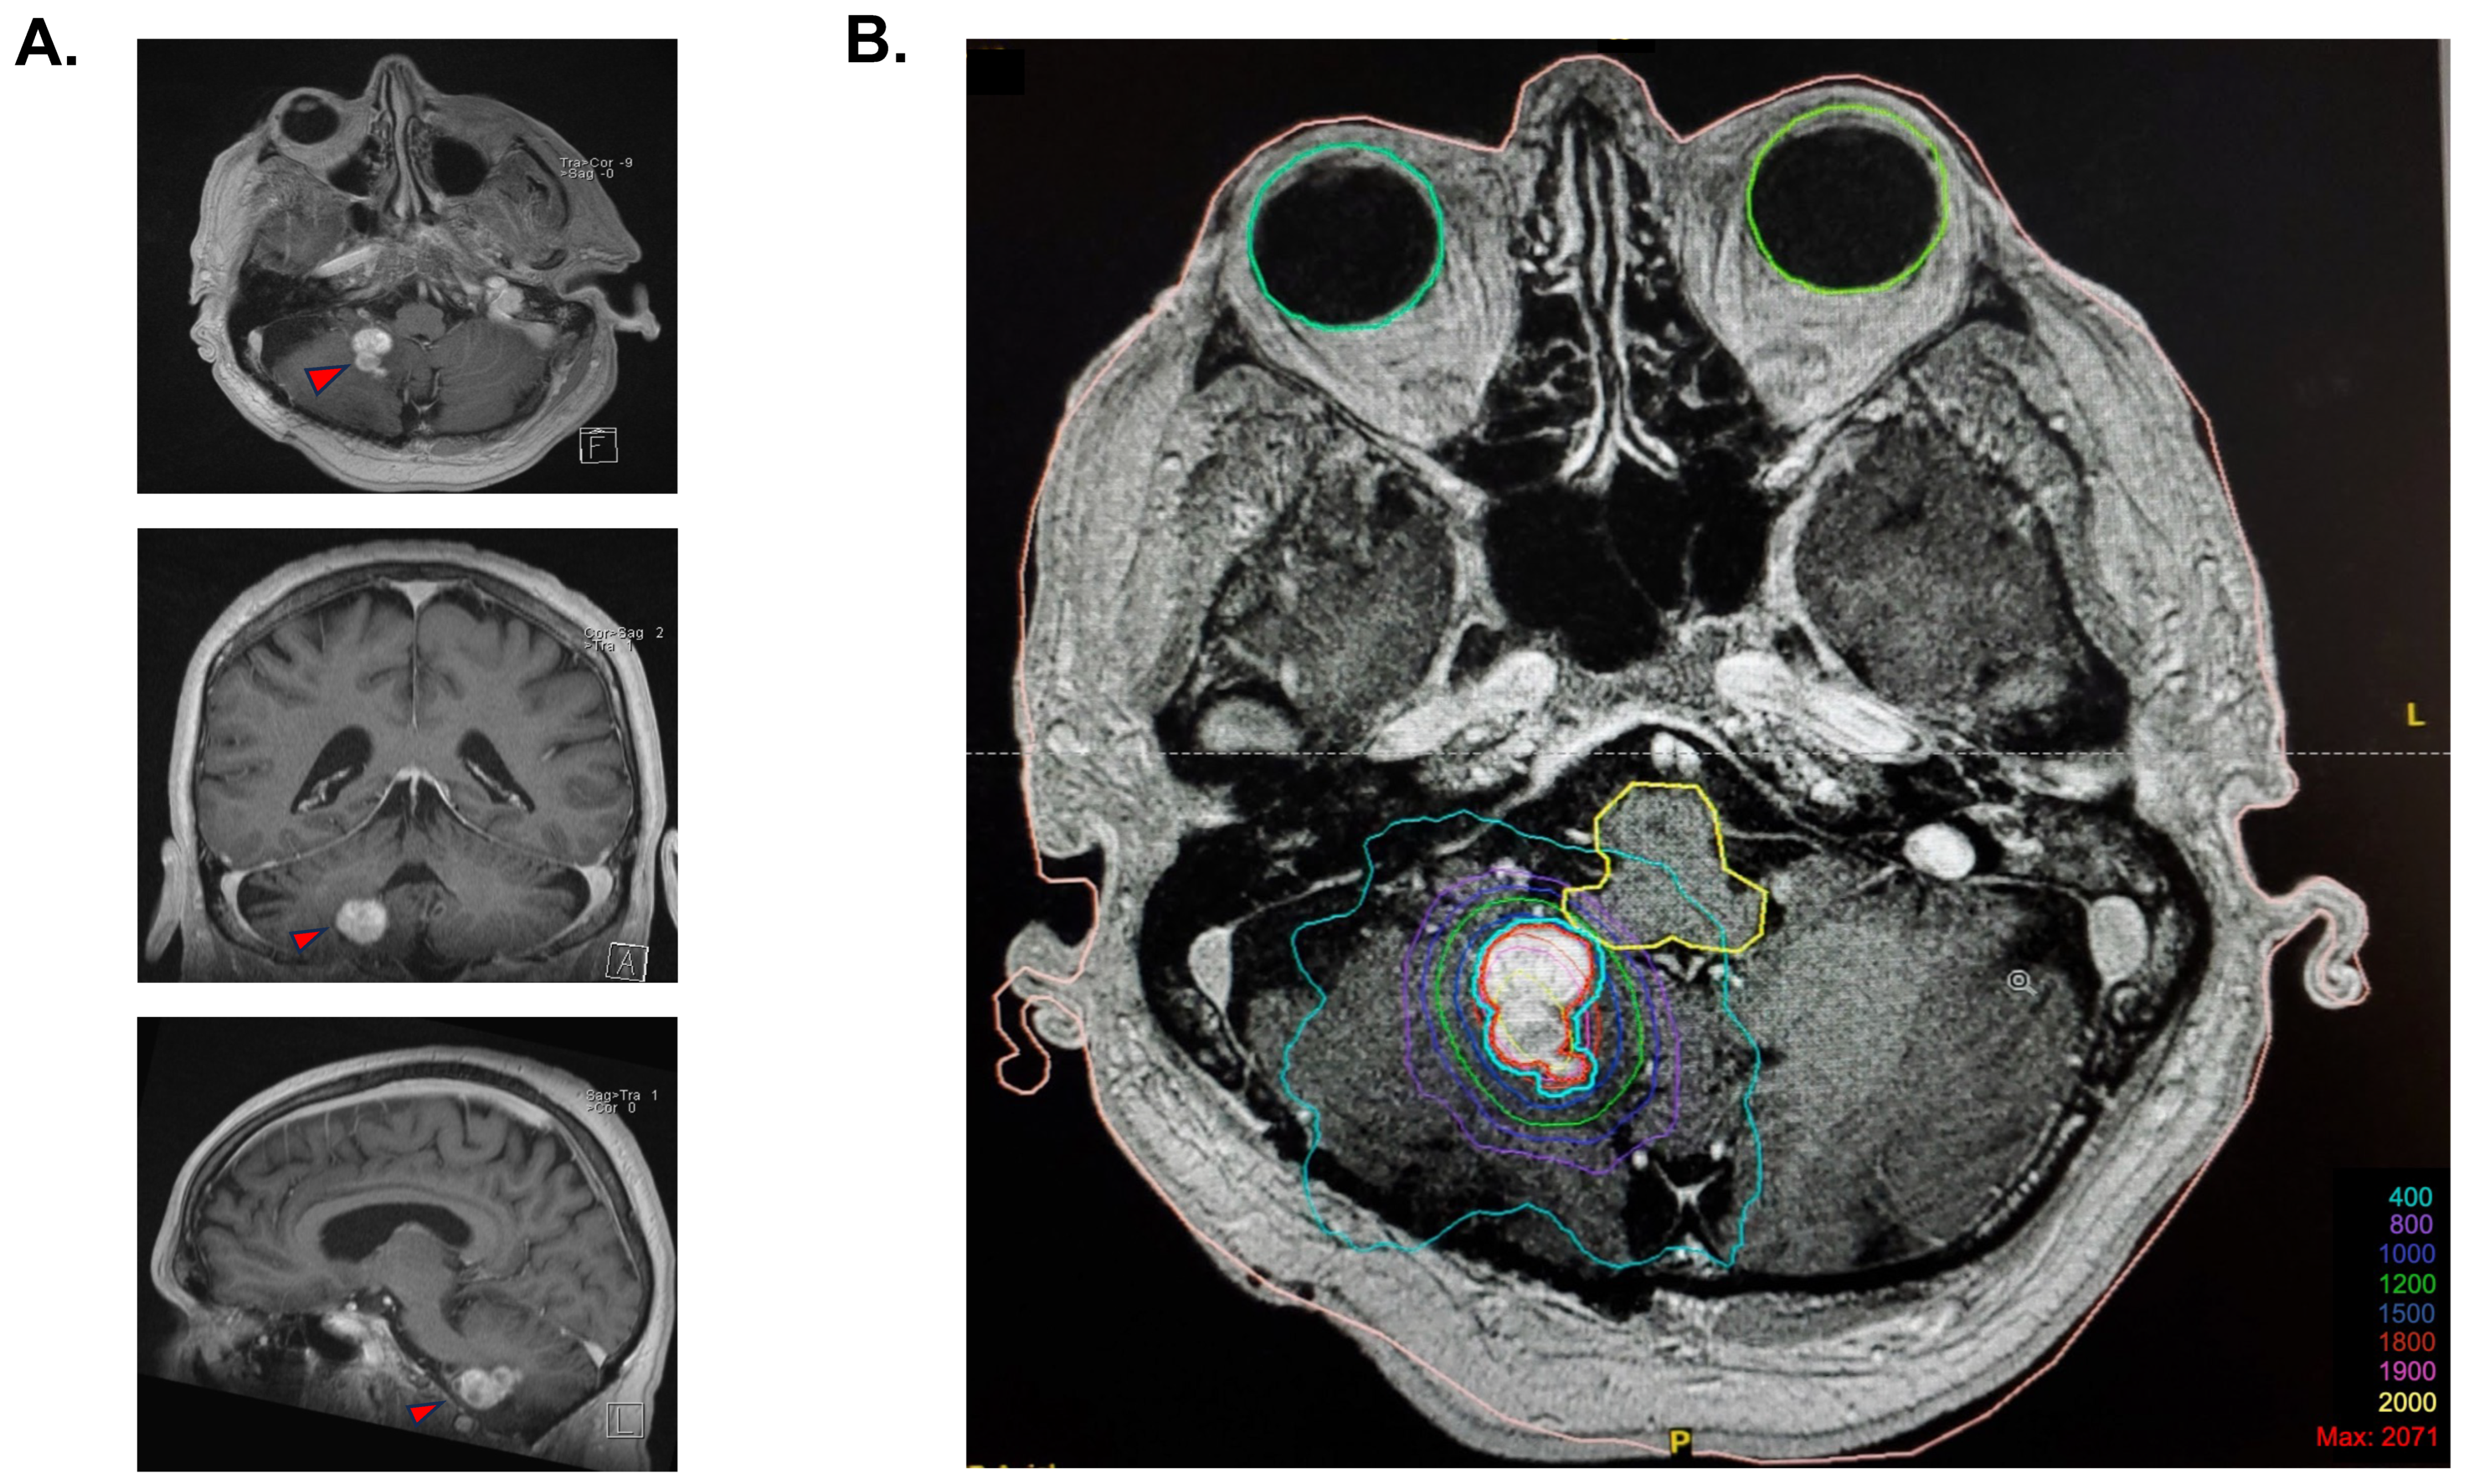

In 2007, a 2 cm progressing enhancing lesion was found, which was stable throughout 2008 and 2009. Minimal progression was again noted in 2010 and 2012. In September 2014, the enhancing portion of the lesion was noted as progressing from 19 × 12 × 15 mm to 20 × 15 × 16 mm (anteroposterior, transverse, cranio-caudal, respectively). A de novo circular, fluid-filled lesion was also noted anteriorly, measuring 8.1 × 15.2 × 13 mm. At the time of radiosurgery planning, the overall lesion measured 25 × 15 mm (AP, T, respectively), with the presence of solid as well as fluid components (Figure 1A).

Figure 1.

Stereotaxic radiosurgery planification. (A) Cerebral MRI T1 images prior to stereotactic radiosurgery, with a demonstration of the polylobulated lesion in the axial view, coronal view, and sagittal view. (B) Isodose coverage of the GTV (in red) for the 18 Gy radiosurgery plan. The blue contour is an expansion of 1 mm of the GTV treated at an 87% isodose because of the proximity with the brainstem. A total of 83% of the tumor volume was covered by the 18 Gy isodose, and 99.9% was covered by the 15 Gy isodose.

Radiosurgery for the slowly progressing lesion was recommended at the neuro-oncology tumor board, primarily because of the deep location of the lesion and its relapsing nature. The procedure took place on 17 December 2014. Immobilization was performed using a stereotactic frame, and an axial MRI T1 post-gadolinium sequence was fused to the planning CT scan for delineation of the target. A dosimetric plan was obtained using the X-Knife treatment planning system. SRS was delivered on a Varian Trilogy unit equipped with a high-definition multi-leaf collimator. The patient received an SRS of 18 Gy, which was prescribed at the 87% isodose, considering that the lesion was situated at millimetric distance to the brainstem to optimize the dose fall-off (Figure 1B). A total of 83% of the tumor volume was covered by the 18 Gy isodose, and 99.9% was covered by the 15 Gy isodose. The gross tumor volume (GTV) was 3.77 cm3. The treatment volume ratio (TVR) was 1.2, and the prescription isodose to target volume (PITV) was 1.0. The maximal point dose to the brainstem was 13.1 Gy. The volume of normal brain that received 12 Gy was 7.9 cm3.